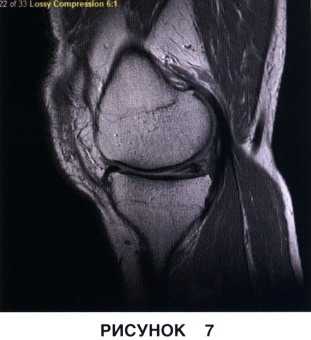

• Неполные разрывы в области верхней или нижней поверхности мениска (рис. 6 и 7)

Длительность хирургического вмешательства обычно зависит от степени повреждения мениска. В среднем артроскопия длится 60 минут. В сложных случаях она может продолжаться 1,5-2 часа. На МРТ справа — разрыв заднего рога мениска, слева — здоровый мениск.